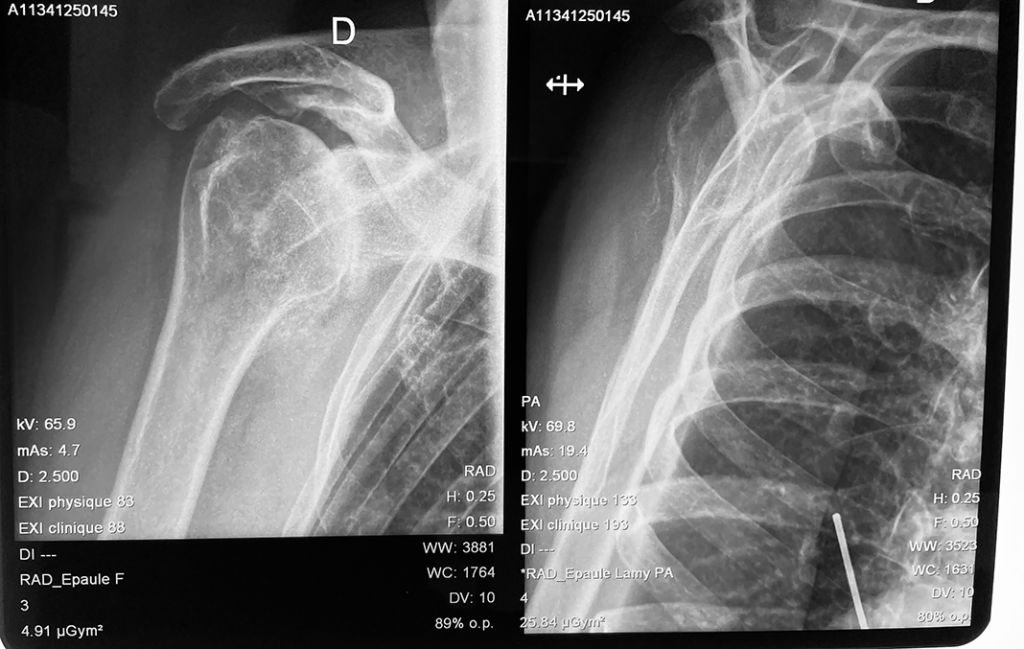

L’arthrose correspond à la destruction du cartilage qui recouvre les surfaces articulaires. Quand cette maladie touche l’épaule, on parle alors d’omarthrose.

On parle d’omarthrose centrée quand la coiffe des rotateurs (tendons de l’épaule) est intacte et que la tête humérale reste en face de la glène de l’omoplate. L’intégrité de la coiffe des rotateurs est indispensable pour une prothèse anatomique sinon il faudra opter pour une prothèse inversée (cf. prothèse inversée)

Pathologie : Arthrose de l'épaule

Omarthrose Centrée - Dr Dumoulin